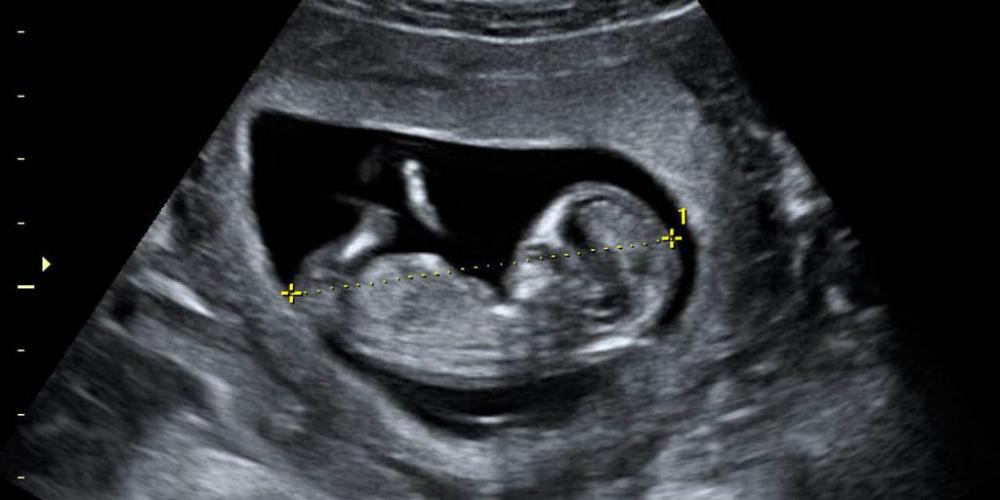

La Dirección de Equidad de Género en Salud junto a la Sociedad Argentina de Ecografías y Ultrasonografía emprende además capacitaciones para que haya profesionales entrenados para interpretar una ecografía, pero también para que las ofrezcan como obliga la ley, es decir, evitando que la madre escuche los latidos del corazón, limitando la información sobre el nuevo ser, entre otras acciones.